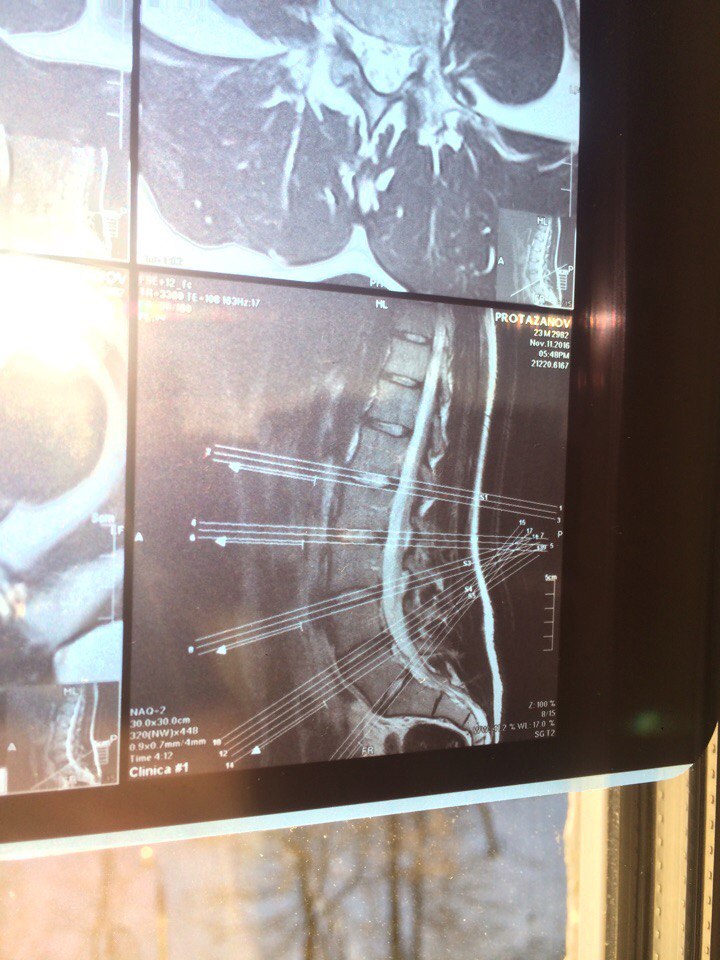

1 это страшное слово "грыжа"